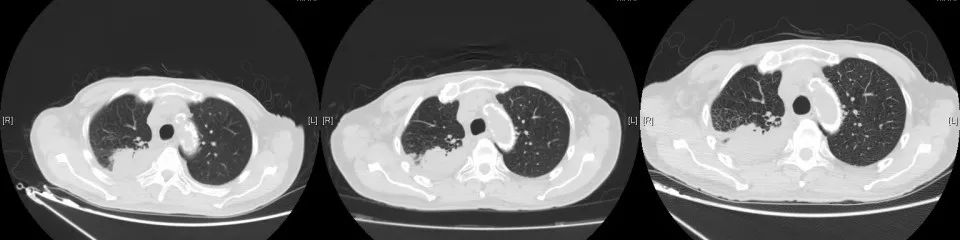

2020年3月复查,病灶再次进展,参考前次基因检测结果,结合临床情况,即开始给予口服吡咯替尼80mg每日一次,2020年4月25因心梗住院治疗。停药约2周。复查示原转移灶稍增大,考虑是否与停药有关,故继续维持吡咯替尼治疗。期间多次复查,病情稳定。局部考虑缓慢进展可能。但综合考虑临床情况,仍继续维持原方案治疗。

2021年5月19日常规复查CT考虑多发肝转移,肺原局部病灶稍进展。考虑吡咯替尼耐药,即予停用。即予“替雷利珠”200mg行免疫治疗1次。无明显副反应。2021年6月因肺部感染、合并心衰去世。

CT变化: